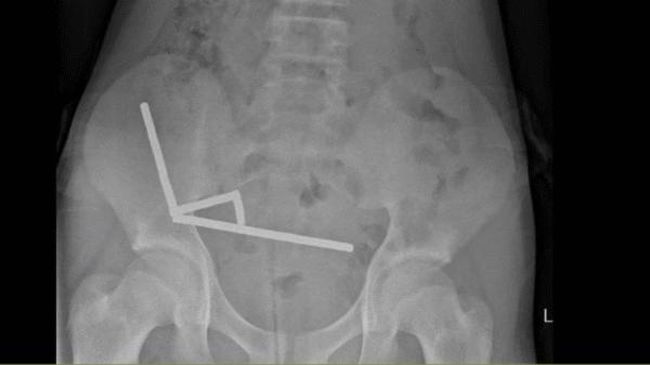

Remaja 13 tahun asal Selandia Baru menelan hampir 200 magnet yang sangat kuat. Akibatnya, dia harus kehilangan sebagian ususnya. (Foto: Lekamalage et al., NZMJ, 2025)

Dilansir detikInet dari Science Alert, remaja tersebut datang ke Tauranga Hospital dengan keluhan nyeri perut dan mengaku telah menelan sekitar 100 magnet seminggu sebelumnya. Namun, hasil pemeriksaan sinar X menunjukkan jumlah magnet jauh lebih banyak dan telah membentuk empat rantai linier di berbagai bagian usus.